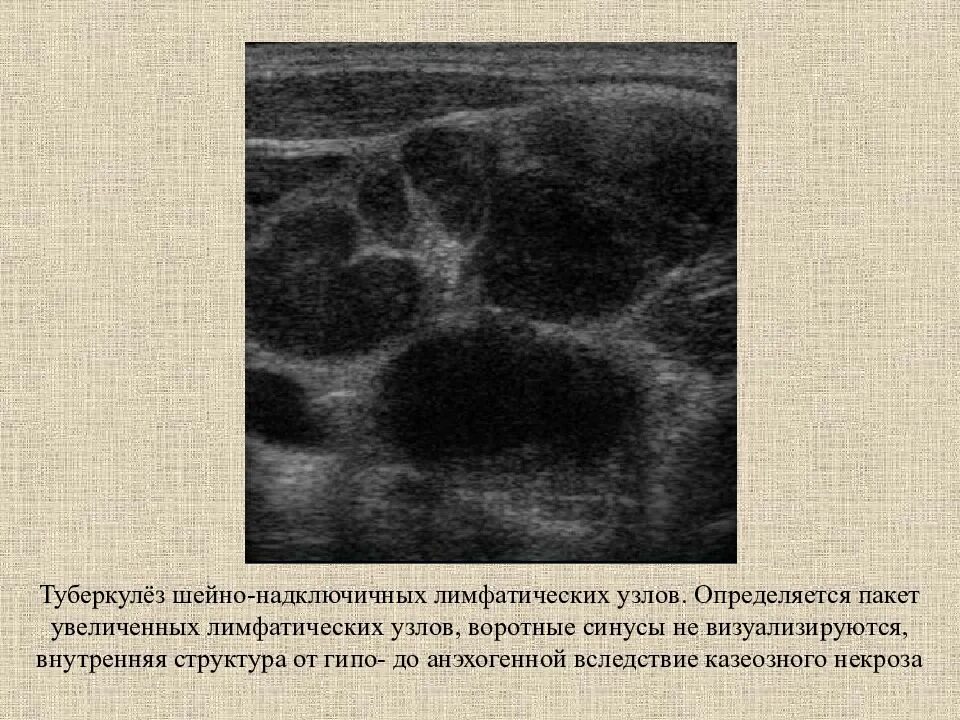

Обследование при увеличении лимфатических узлов